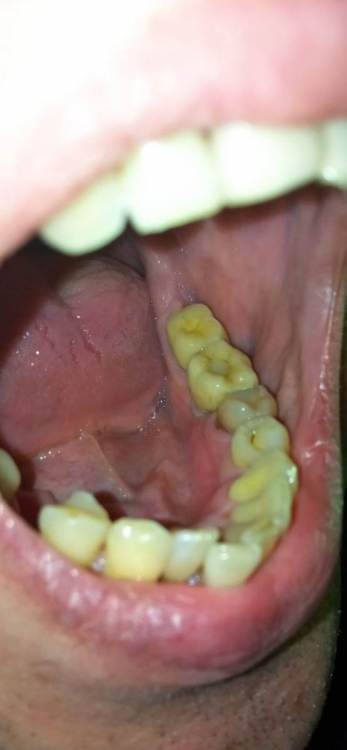

Jonik Опубликовано 29 июня, 2022 Поделиться Опубликовано 29 июня, 2022 Здравствуйте! Поставили коронку на временный цемент, недавно она отвалилась, нужно идти фиксировать на постоянный цемент но коронка мне не совсем нравится. Слой керамики в некоторых местах выходит за пределы металлического основания. Где то слой керамики заглажен к металлу, а где то имеет утолщение. Можно ли фиксировать такую коронку или переделывать. Если поставить эту коронку, могут ли потом возникнуть проблемы с гигиеной или с десной? Ссылка на комментарий

Jonik Опубликовано 30 июня, 2022 Автор Поделиться Опубликовано 30 июня, 2022 31 минуту назад, Doc сказал: Тут весь вопрос в том, что это было. Если керамическое плечо, то это нормально и даже когда-то приветствовалось. Если же техник просто металл не дотянул, а потом решил керамикой доляпать, то это совсем другой вопрос. Как во рту сидит? По десне все хорошо, либо над, либо глубоко под? Где уступ? Коронка точно без плеча. Когда была первая примерка врач отправил коронку на корректировку, сказал что нужно поправить немного. Может как раз это и был недотянутый метал. Как во рту сидит мне не нравится, местами под десну заходит. Ближе к уступу коронка кажется массивной, имеет утолщение возле десны, как бы наплывает на десну, приходится промывать ирригатором. Ссылка на комментарий